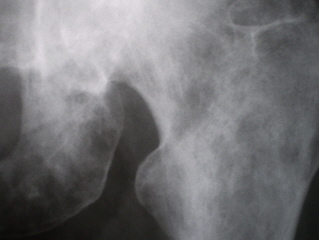

Иллюстрация 2 – определяются множественные очаги деструкции костной ткани, хорошо дифференцирующиеся в области седалищной кости и её ветви, в области шейки, проксимального мета – диафиза левой бедренной кости.

Иллюстрации 7, 8. Кроме седалищной кости и её ветви очаги деструкции хорошо дифференцируются в области головки, шейки, большого вертела и проксимального мета – диафиза левой бедренной кости. Очаги полиморфны